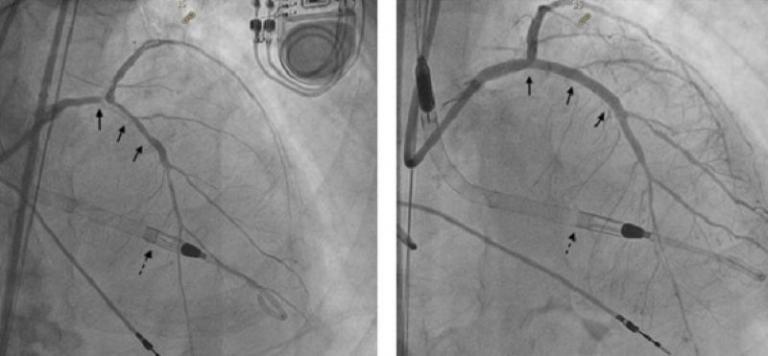

▲醫療團隊在治療中採用 Impella(虛線箭頭)作為循環支持。血管攝影影像顯示,病人手術前左主幹顯著狹窄合併嚴重鈣化(左圖實心箭頭);完成處置後,血管支架擴張良好,血流明顯改善(右圖實心箭頭)。 (圖/記者蔣彤雲攝)

手術由心臟內科連朕緯醫師擔任主責,連朕緯醫師說明,病人的冠狀動脈攝影顯示病灶高度複雜,包含左主幹遠端狹窄80%、前降支近中段狹窄80%、左迴旋支近段狹窄 70%,且血管鈣化嚴重,無論以心導管介入治療或外科開刀都乘載極高的手術風險,使治療規劃更具挑戰,考量病人心臟功能脆弱,心臟科團隊討論後選擇於 Impella 循環支持下進行介入治療。

連朕緯醫師指出,手術採用 1.5 毫米旋磨鑽頭處理鈣化病變,全程以血管內超音波導引支架置放,並於左主幹分叉位置採符合國際標準治療指引技術置放三支藥物塗層支架,成功優化冠狀動脈血流,治療期間在 Impella 支持下,病人血流動力維持穩定,病人於術後監測狀況良好,無嚴重併發症,住院 9 日即順利出院,出院後一個月的心臟超音波追蹤顯示左心室射出分率從30%進步至45%,顯示此項技術在重症心血管照護中具高度效益